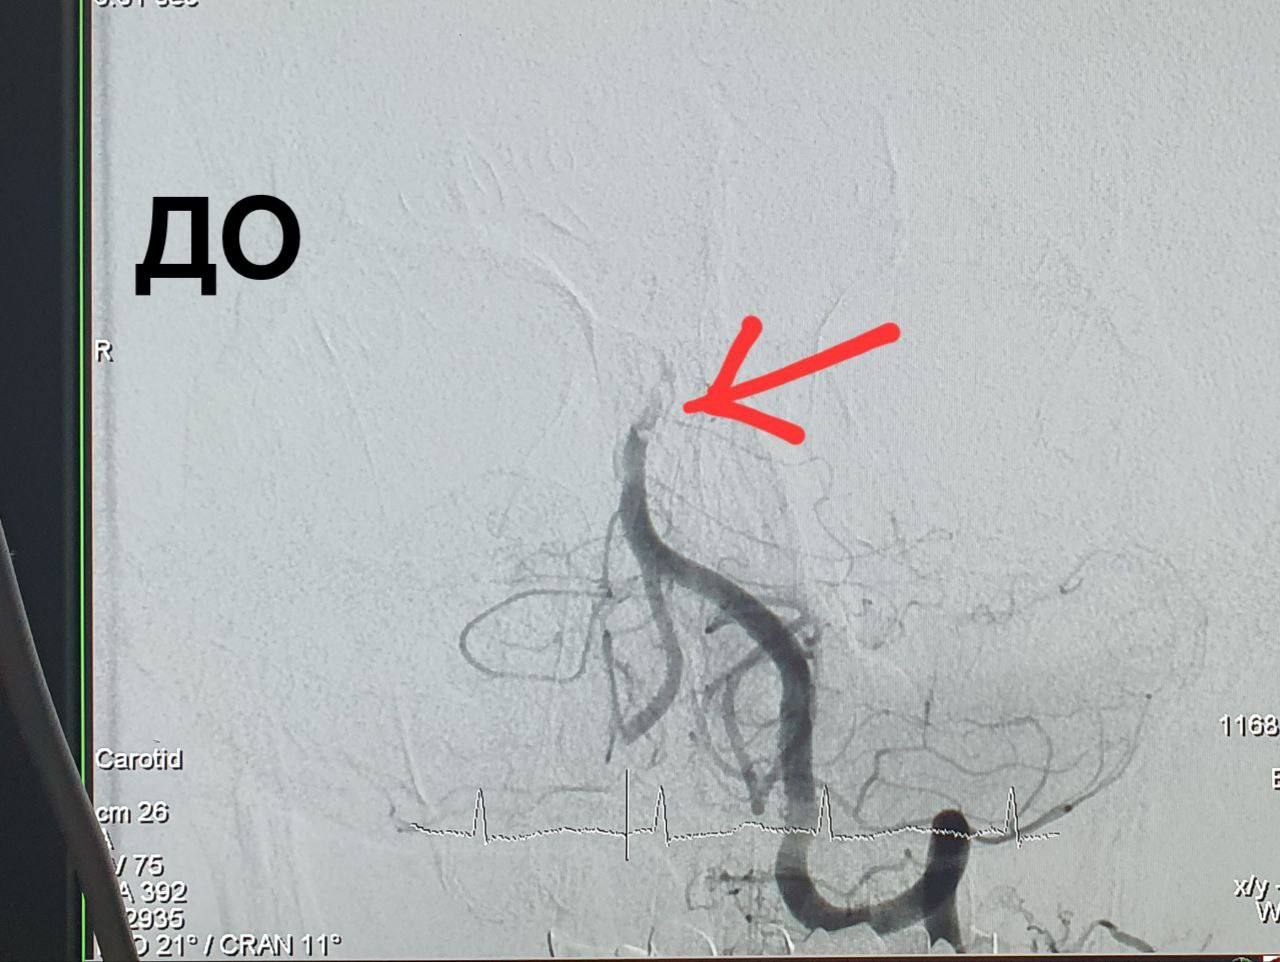

59-летнему оренбуржцу стало плохо на работе. Он пожаловался коллегам на головную боль и упал в обморок. Сначала мужчину доставили в городскую больницу им. Н.И. Пирогова, где после компьютерной томографии закупорка базилярной артерии.  Эта артерия образовывается при слиянии двух позвоночных артерий и снабжает кровью задние отделы мозга.

После консультация с главным ангионеврологом министерства здравоохранения Оренбургской области Александром Чирковым и главным внештатным специалистом по рентген-эндоваскулярным диагностике и лечению Алексеем Деминым пациента срочно доставили в Оренбургскую областную больницу им. В.И. Войнова для  открытия артерии головного мозга в условиях рентген-хирургической операционной. На тот момент мужчина был в крайне тяжелом состоянии и дышал при помощи ИВЛ. Хирурги во время операции извлекли из артерии большое количество тромбов и восстановили ее проходимость. Такую сложнейшую операцию в Оренбуржье провели впервые.